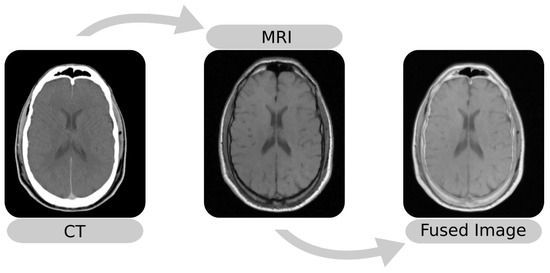

The image fusion (Figure 1) maps images into the same coordinate system and then blends the aligned result into an output image. Among the methods for image fusion, characteristics such as imaging modalities determine the performance of a procedure. For example, methods that use the Mean-Squared Difference (MSD) as the optimization metric perform better in single-modality fusion [10,11]. Thus, it is essential to know the performance of these techniques, especially in applications such as SEEG that involve external objects.

Figure 1. Example of multi-modal image fusion between an MRI and a CT. The images were taken from Patient 001 of the RIRE dataset [12].